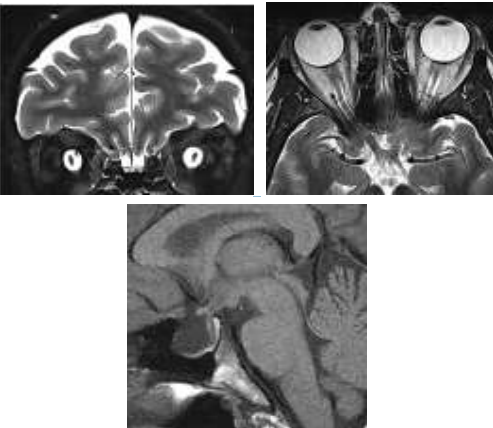

Paciente do sexo feminino, 33 anos, obesa, apresentando queixa de turvação visual progressiva e cefaleia de difícil tratamento. Foi avaliada por oftalmologista que descreve edema de papila. Realizou RM de crânio com os achados abaixo.

Enunciado 3028009-1

Assinale a alternativa que corresponde ao provável diagnóstico para o caso acima